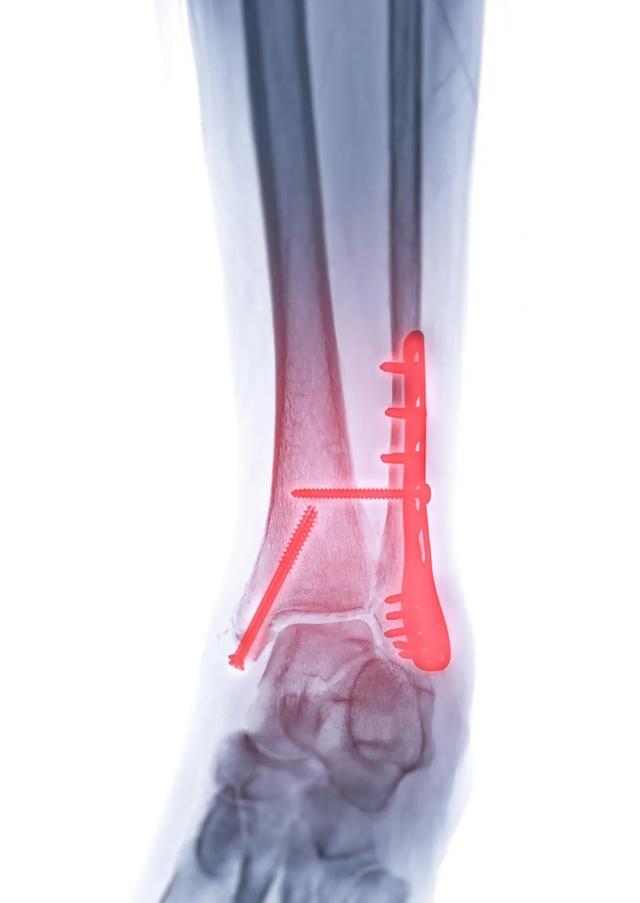

骨折手术后出现并发症:如伤口感染、内固定排异反应、骨髓炎等,需要及时取出内固定。

关节部位的钢板内固定:如肘关节、腕关节、膝关节、踝关节等,若内固定放置的位置影响关节活动,或固定的螺钉穿出关节面,此时内固定应及时取出,否则会造成关节畸形、关节活动障碍、疼痛等,甚至有发生创伤性关节炎的可能。